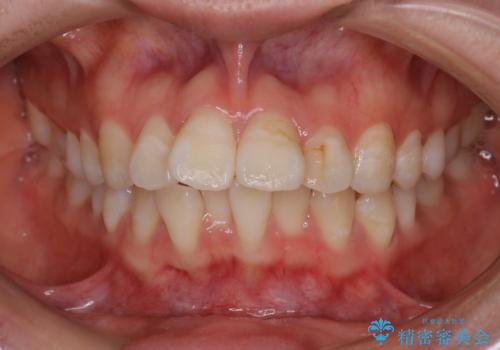

- 前歯のがたつきと口元を気にされて来院されました。

上下4番目の歯を抜歯してがたつきを改善しながら口元を下げる治療計画を立てました。